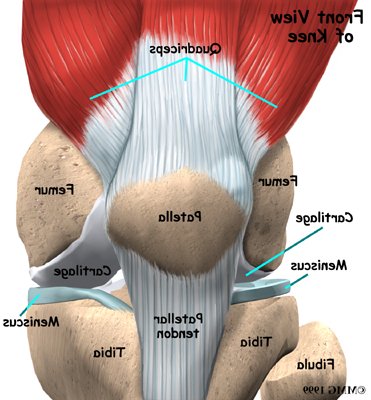

Please annotate this diagram with the site(s) of swelling or tenderness.

Right Knee

Notes: -

Left Knee

Notes:-